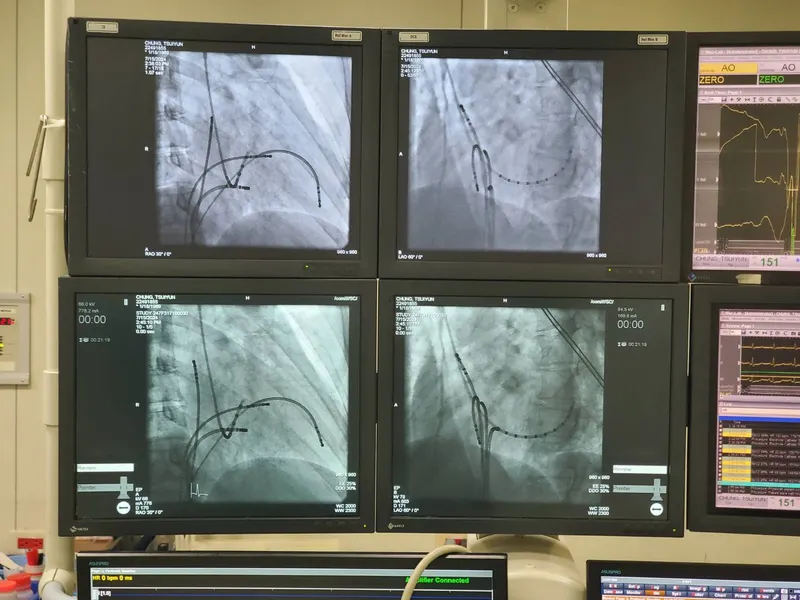

心為君主之官,本不受病,由於心臟很熱,除了先天性結構的問題產生的疾病之外,不曾聽到過心臟癌的疾病,而會造成胸痺心痛短氣的問題,是出在上焦橫膈膜、縱膈膜、心包的地方有寒濕、停水堆積造成種種不適的症狀。西醫對於心臟結構性的問題就是藉由手術來治療,比如心臟冠狀動脈手術、冠狀動脈繞道手術、經皮冠狀動脈介入治療(簡稱 PCI)、動脈粥狀硬化斑塊切除術、心臟瓣膜手術、瓣膜修補手術、經導管主動脈瓣膜置換手術等等,而中醫是沒有開刀的,中醫的標準是將心臟不適症狀治療到一定的程度,將可能堵塞在動脈裡面的東西,或是寒濕、積水去掉就可以了,所以從中醫的角度來看,通常都不是心臟本身結構出現問題。病患如果一開始給西醫手術治療心臟病後,如果再想回到中醫治療時,通常效果都很差,因為心臟原本的結構已經被置換了,當中醫把寒濕、水去掉讓心臟恢復正常結構後,被置換過的組織(比如心瓣膜)大小就與原本的不合,倪師常常用玻璃罐與瓶蓋做比喻,心臟好比是玻璃罐本體,瓣膜好比是玻璃瓶瓶蓋,當瓶蓋被換大一點之後,就無法與原本大小的瓶身相吻合。所以在此篇章中,仲景先師治療的重點就分別在橫膈膜、縱隔膜與心包這三個位上,利用簡單的幾味藥,把裡面的水、寒濕去掉,另外阻塞在血脈中的東西也可以去掉,基本上就按照出現的症狀來對症下藥,不用管那一種病毒、細菌造成的炎症,因為只要把「環境改善」了,一切細菌病毒就無法在此滋生,加上倪師常用的幾個穴道:公孫、內關、天突、巨闕、關元、督脈中樞穴(T10),肺俞等等,針藥並施,效果特快。

PSVT(陣發性上心室頻脈),簡單說就是突發性的心悸,原因來自心臟多了一條不正常的"神經”,也就是說原來我從小就有先天性心臟病,但我卻不知道。

27歲時心悸發作135下/分鐘,以為是喝咖啡造成的,做過心電圖、運動心電圖、24小時心電圖……一切正常,什麼都檢查不出來。